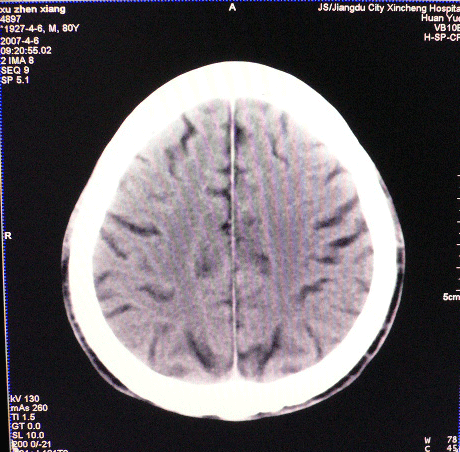

以下是引用狙击手在2007-4-8 22:45:00的发言:[br]出血?从患者的症状考虑病灶应该在左侧大脑半球的基底节区或颞顶部,如此小的病灶引起上述症状的可能性不大,患者可能有梗塞(时间短,目前ct还看不见)或是tia发作,再者像这样的线条形出血的确不多见,但还是有可能的,曾经碰到有外伤类似出血,复查后消失,所以还是慎重一点,短期复查即可。

以下是引用dyqct在2007-4-8 16:25:00的发言:[br]支持左侧放射冠区少量出血。